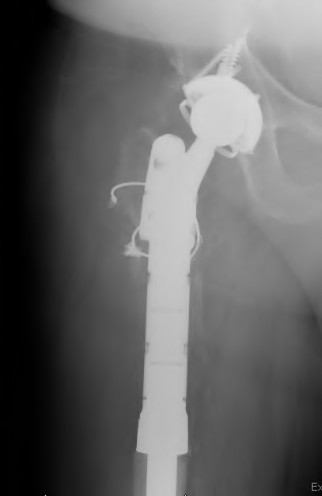

The radiograph demonstrates a periprosthetic femur fracture extending to the tip of the stem. The long spiral fracture is consistent with a loose implant. The bone stock is sufficient. Therefore, this fracture pattern would classify as a B2 using the Vancouver classification system. The Vancouver classification for periprosthetic femoral fractures is simple yet incorporates all the pertinent factors such a location, stem fixation, and bone stock. Type A is a trochanteric fracture- lesser or greater. These can be treated non-operatively usually and ORIF if symptomatic. Type B fractures are around or just below the stem and are subdivided into three types. Type B1 is a fracture with a well fixed stem.

The treatment is cable plating or allograft struts or a combination of the two. Type B2 is a fracture with a loose stem with good bone stock. The treatment is a cementless porous coated long stem atleast two diameter length past the

fracture site. Type B3 is a fracture with a loose stem and comminution. For younger patients, use cementless porous coated long stems with allograft struts. For older patients, consider a tumor prosthesis. Cement fixation is sometimes necessary Type C is a fracture well below the stem tip. These can be treated independently of the prosthesis.

A 72-year-old male presents 2 years status post fixation of an impending pathologic right femur fracture due to metastatic renal cell carcinoma. He is minimally ambulatory due to pain. Despite radiation therapy, there has been progression of the lesion with extensive cortical bone loss, which is shown in Figure A. A proximal femoral replacement arthroplasty is performed without complications, and is demonstrated in Figure B. Which of the following is true regarding this patients post-operative course?

Figure A shows a lytic lesion of the proximal femur with an intramedullary implant. Figure B shows a proximal femoral replacement.